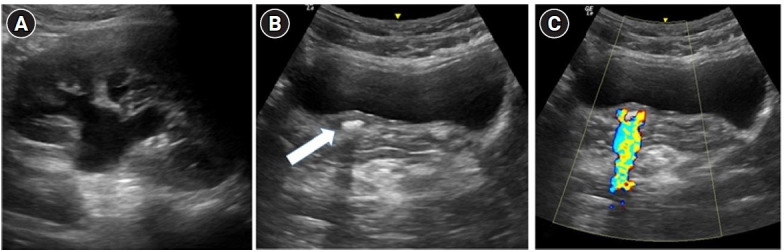

Symptomatic urolithiasis is a common cause of emergency department visits, with noncontrast computed tomography considered the imaging gold standard. According to the current guidelines, point-of-care ultrasound (POCUS) is limited to evaluating hydronephrosis as a secondary sign of acute ureteral stones. However, the use of POCUS to detect ureteral stones may lead to decreased radiation to the patient and a more rapid diagnosis. This case series describes 10 patients with suspected symptomatic urolithiasis who were diagnosed accurately by emergency physicians using POCUS to detect obstructive ureteral stones. In three of the cases, POCUS significantly changed the patient's management. This article also describes the proper techniques for the emergency physician to learn to master POCUS for ureteral stone detection.